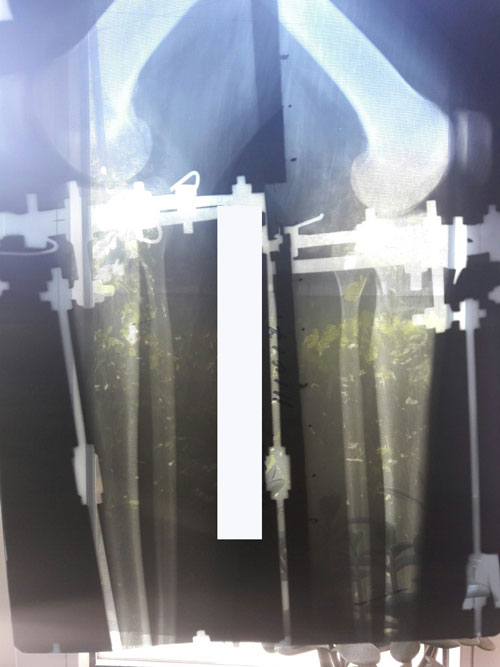

Дата операции 19.07.2017г

Дата снятия аппаратов 17.10.2017г.

Срок лечения 88 дней.

Только доктор Онипко может так красиво устранять Ротацию! Браво ему!!!